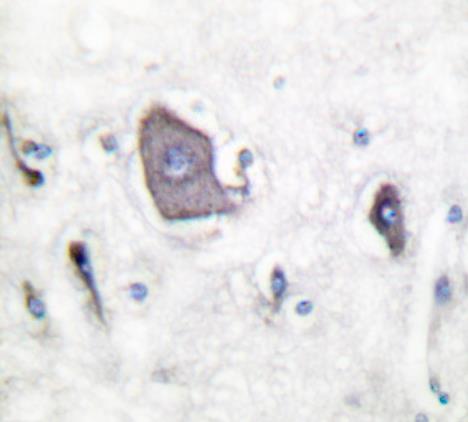

Formalin-fixed;paraffin-embedded human brain tissue stained for TrkB (Phospho-Tyr705) using 52705 at 1/100 dilution in immunohistochemical analysis.